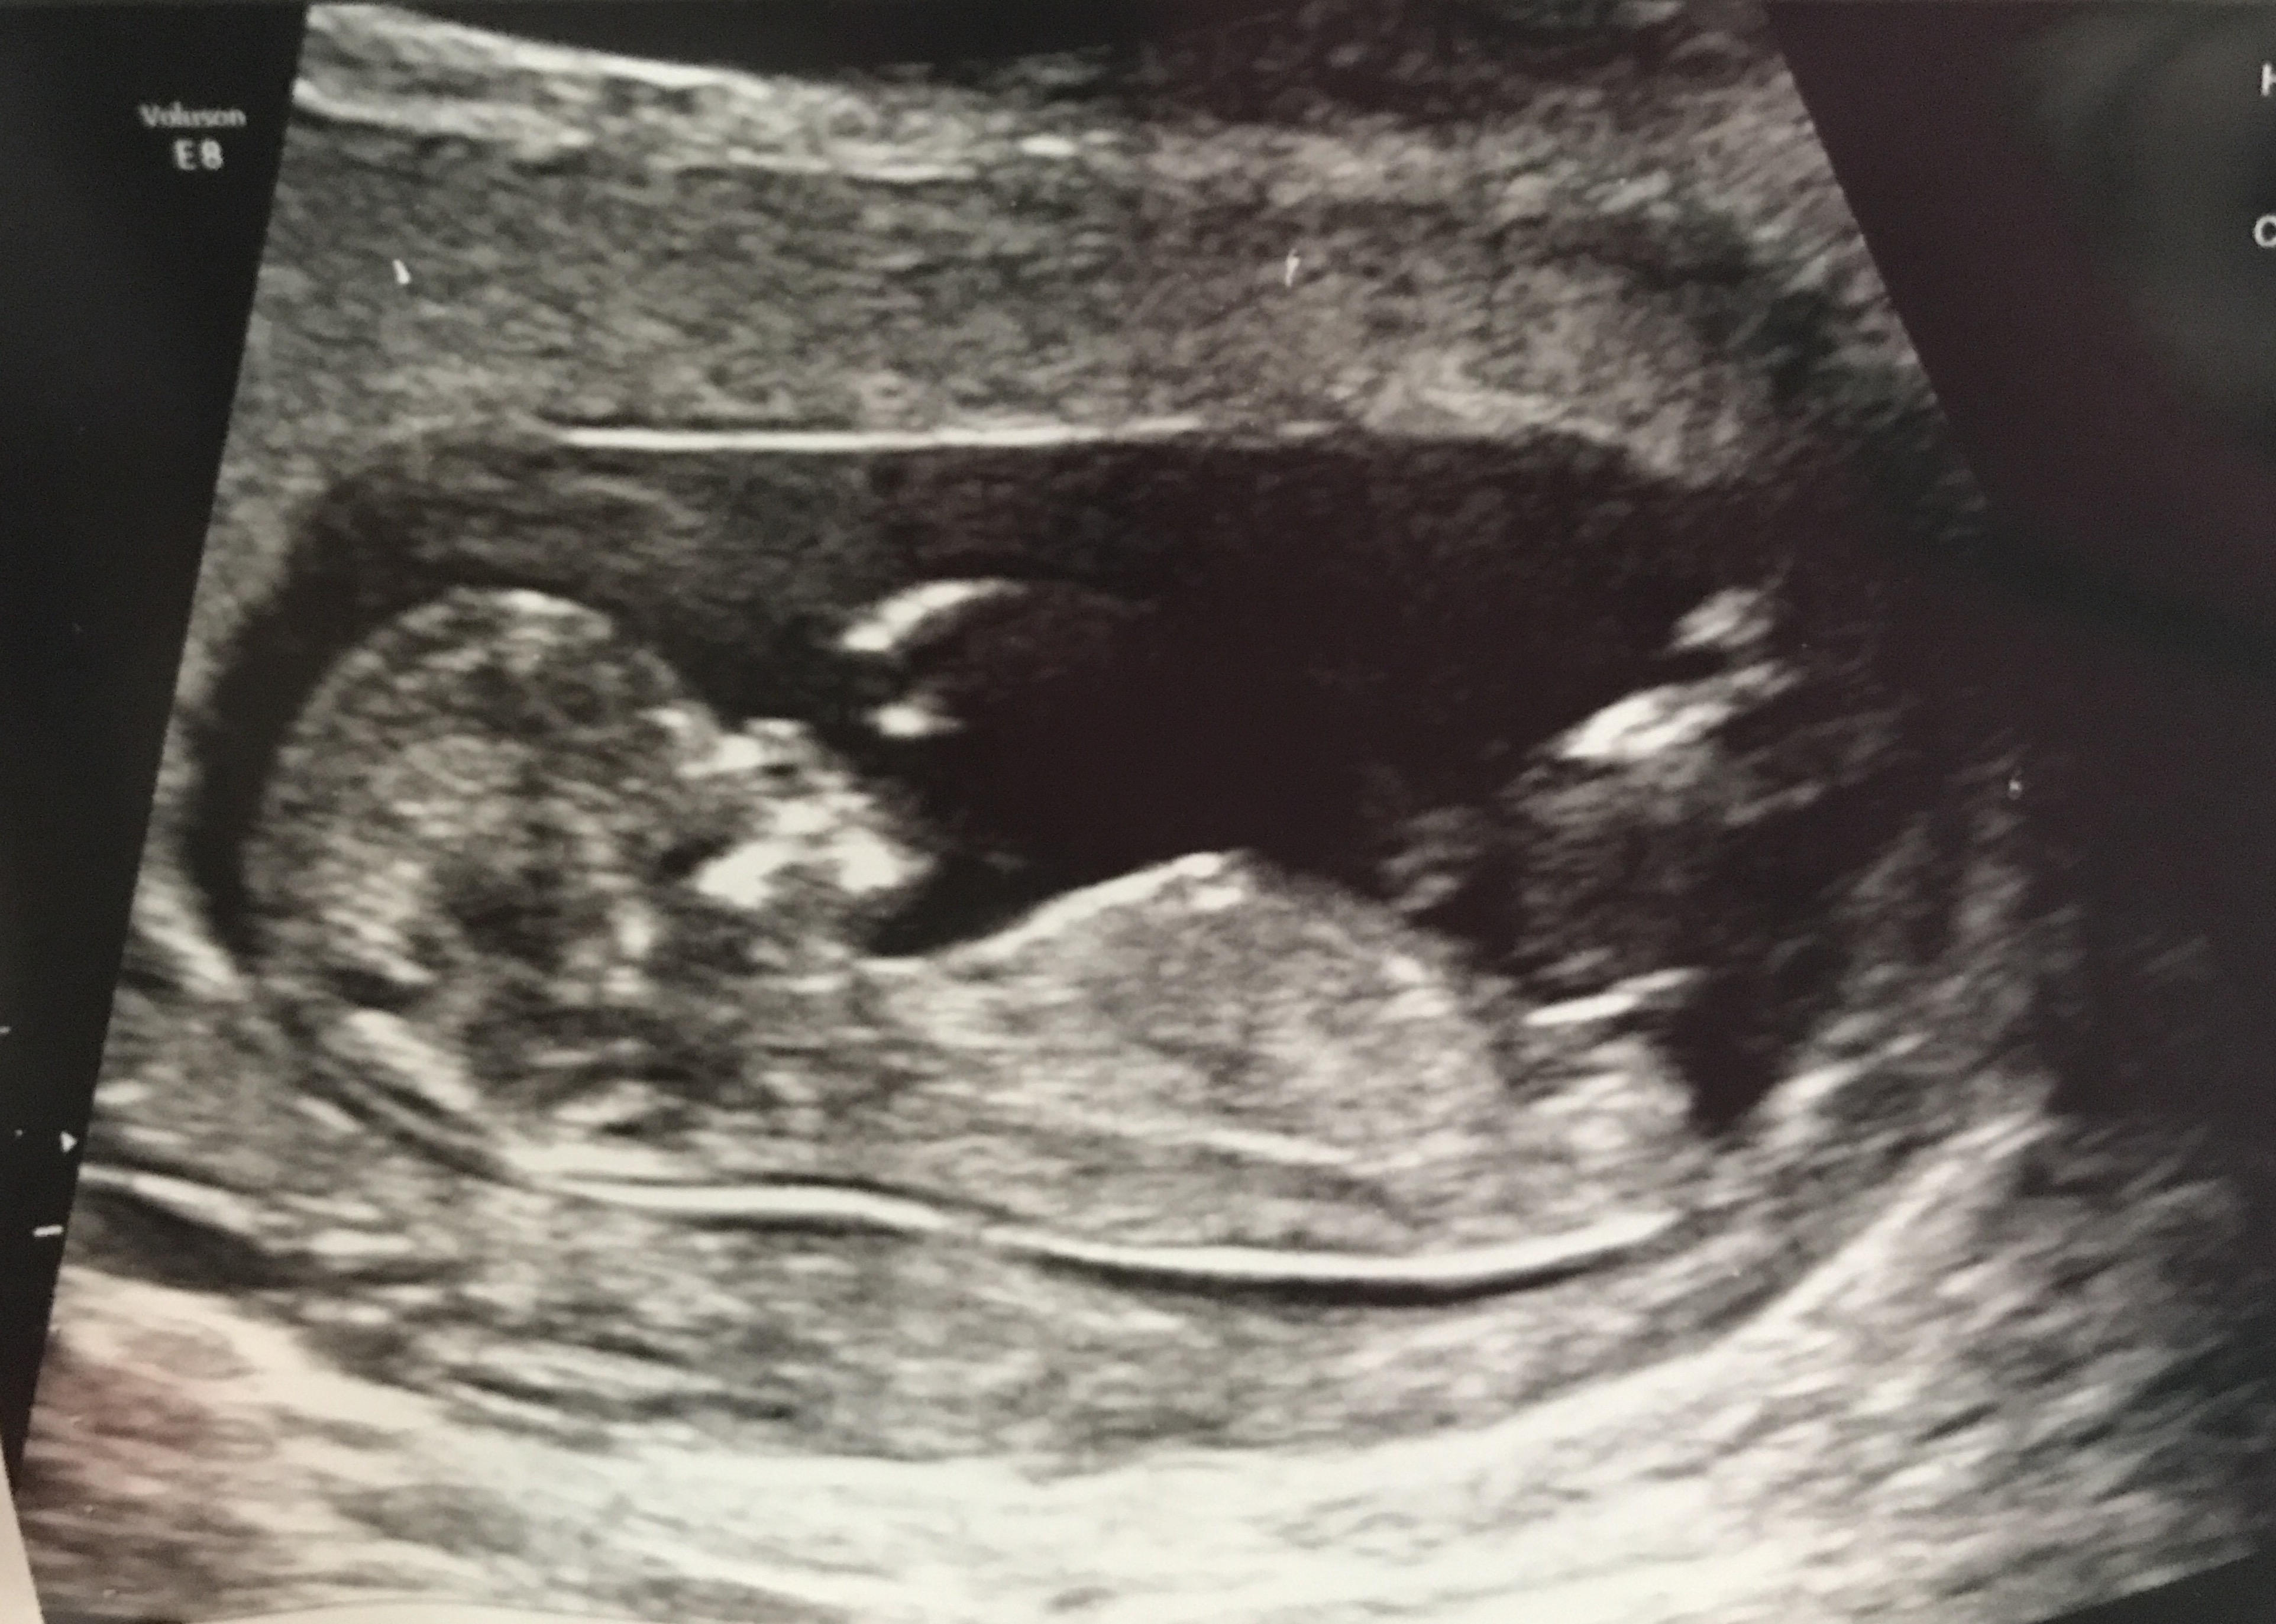

Boy or girl at 12w2days??